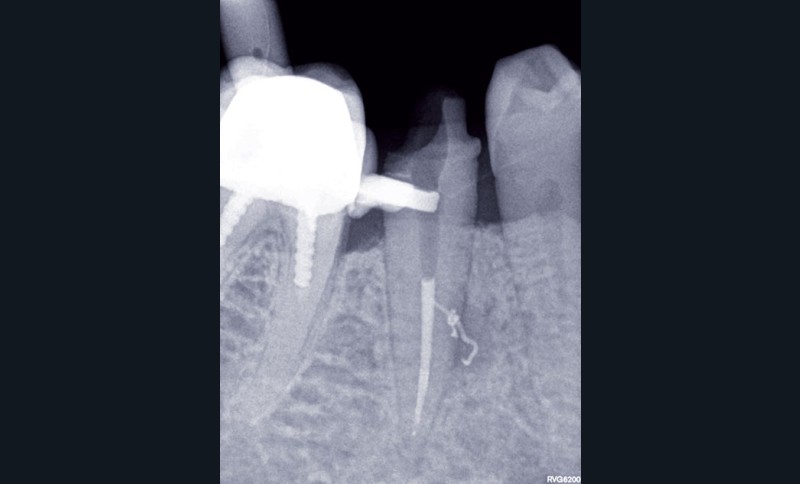

1. Une radiographie rétro-alvéolaire centrée sur 45 met en évidence une reprise de carie sous la restauration en composite et une lésion inflammatoire périradiculaire d’origine endodontique (LIPOE). Le test de vitalité est négatif.

3, 4, 5. La restauration est déposée, les tissus carieux éliminés et la cavité d’accès aménagée avant la réalisation du traitement endodontique. La radiographie postopératoire permet de visualiser l’obturation du canal latéral en regard de la LIPOE.